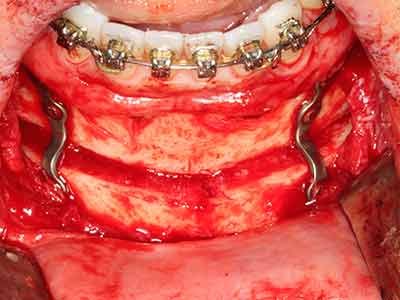

Bei der Knochenblockentnahme zeigen sich weitere Vorteile für die Piezochirurgie: Neben der bereits beschriebenen hohen Präzision bei der Osteotomie stellt sich gerade die Verwendung der dünnen Sägespitzen als besonders materialschonend heraus. Bei der Verwendung insbesondere von Lindemannfräsen sind mit deutlich höheren Entnahmeverlusten durch die dickere Instrumentenspitze zu rechnen (Lakshmiganthan, Gokulanathan et al. 2012). Die insbesondere bei retromolar entnommenen Blocktransplantaten notwendige basale Abtrennung wird durch speziell hierfür vorgesehene rechtwinklige Sägen erleichtert, so dass die Piezochirurgie als präzises, übersichtliches und sicheres Verfahren zur retromolaren Knochenblockgewinnung angesehen wird (Happe 2007) (Abb. 1-12).

Abb. 1: Präparation eines ent-sprechenden Knochendeckels mit dem Piezomed.

Abb. 3: Die basale Abtrennung des Blocks wird durch speziell abgewinkelte Aufsätze erleichtert.